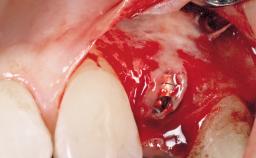

A 30-year-old female patient was referred to the office for the treatment of tooth 11. Her chief concern at the initial visit was to inquire, “Why is my tooth pink?” Upon clinical examination, it was determined that tooth 11 had a previous history of trauma and that the clinical crown had become noticeably pink in color as a result of internal resorption. This diagnosis was confirmed radiographically, indicating a large radiolucency involving the central and distal portions of the clinical crown. It was determined that restoration of this tooth was not possible, and that extraction was indicated. The presence of a mid-line diastema, which the patient wanted to reproduce, directed the treatment plan for tooth replacement utilizing a dental implant.

Bone Augmentation Horizontal|Simultaneous

Augmentation Materials Autogenous chips|Membrane

Placement Protocol Immediate implant placement

Socket Morphology Single-root socket

Socket Integrity Sufficient, with intact bone walls

Bone Volume Sufficient, with intact walls